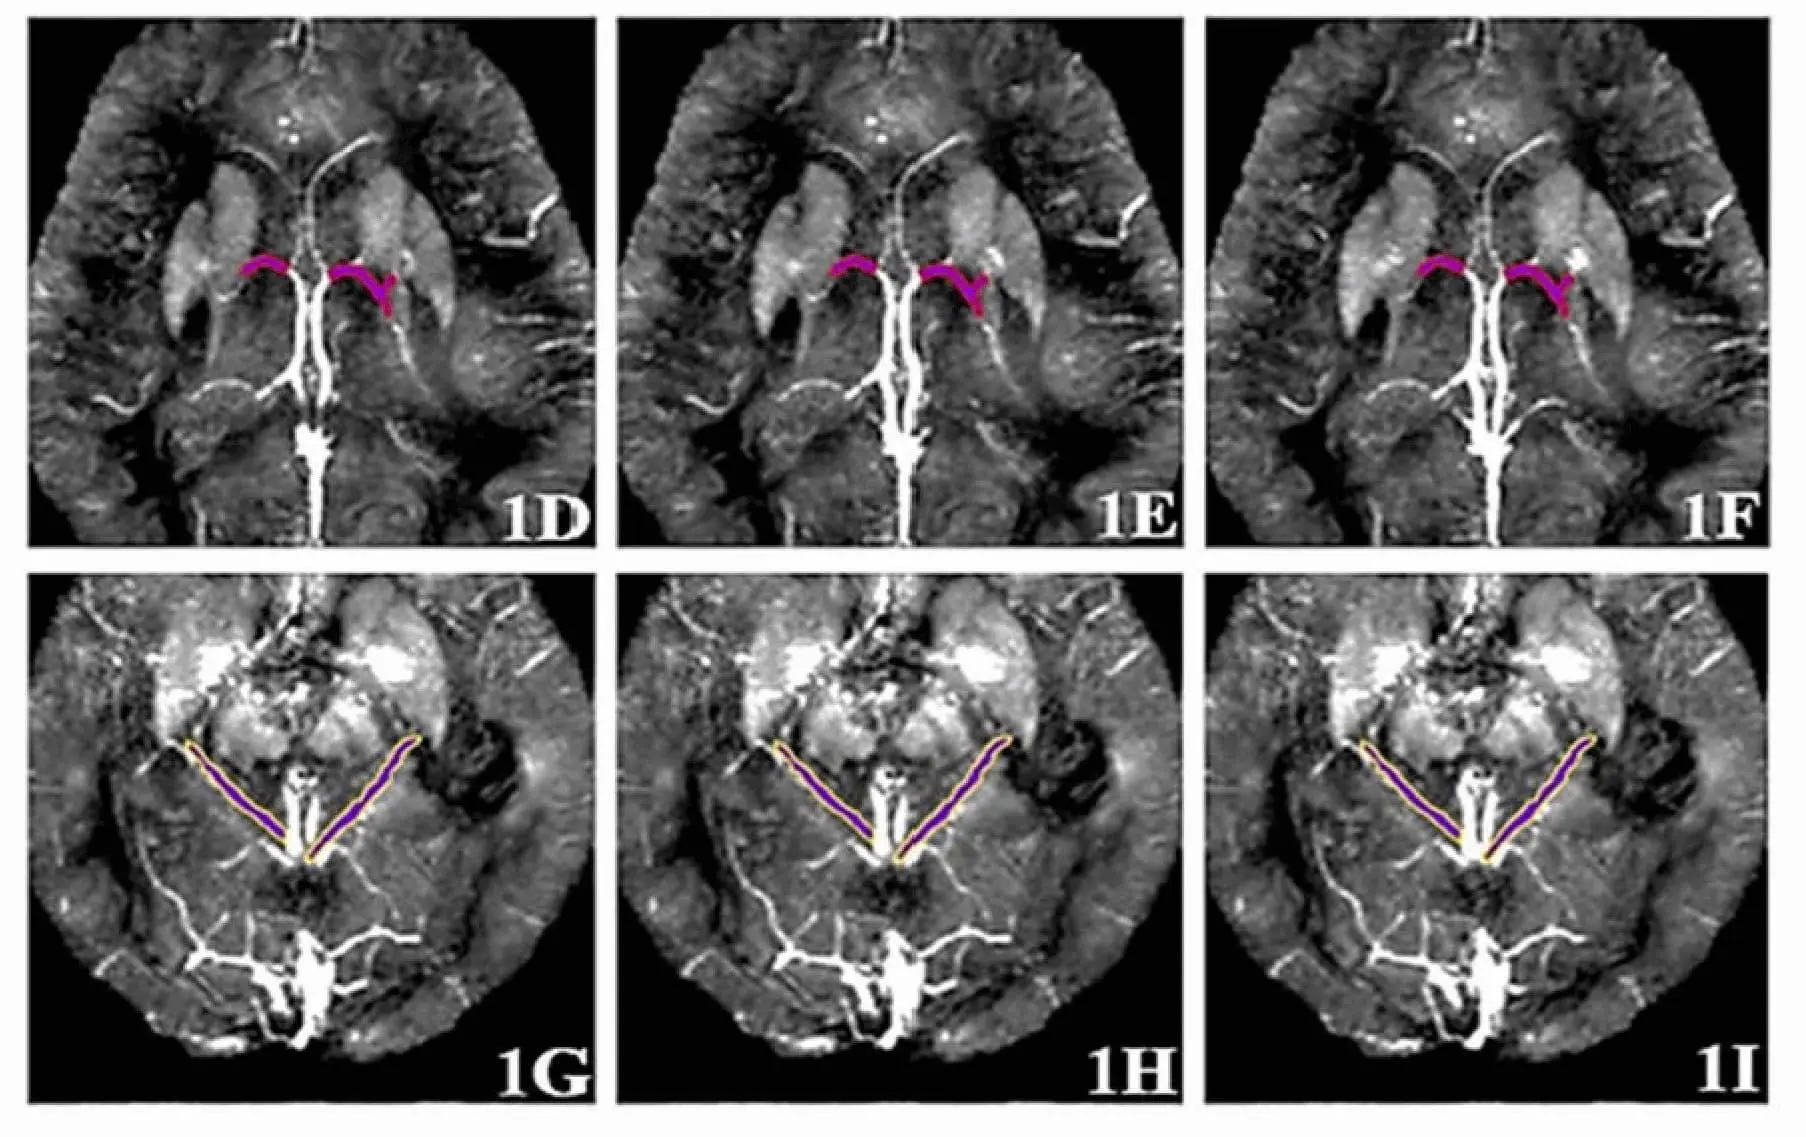

Команда российских исследователей предложила принципиально новый и уникальный подход, заключающийся в комплексном анализе состояния вен головного мозга с использованием магнитно-резонансной томографии с контрастированием и современных технологий машинного обучения. Если ранее специалисты ограничивались оценкой четырех вен, то новая технология учитывает параметры уже шести вен и их магнитной восприимчивости, что заметно повышает достоверность оценки.

Во время проведения процедуры пациенту внутрь организма вводят безопасный контраст на основе гадолиния, что обеспечивает максимально четкое отображение структуры сосудов. После МРТ специалисты измеряют параметры восприимчивости в шести венах, получая жизненно важные данные о состоянии кровоснабжения и насыщенности тканей кислородом. Именно эти показатели зачастую первыми изменяются при формировании ранних патологических процессов, свойственных болезни Альцгеймера.